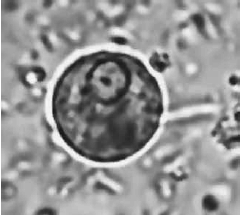

A imagem ilustra o achado de um exame parasitológico de fezes de um paciente cujo diagnóstico é de doença causada pelo seguinte agente etiológico: